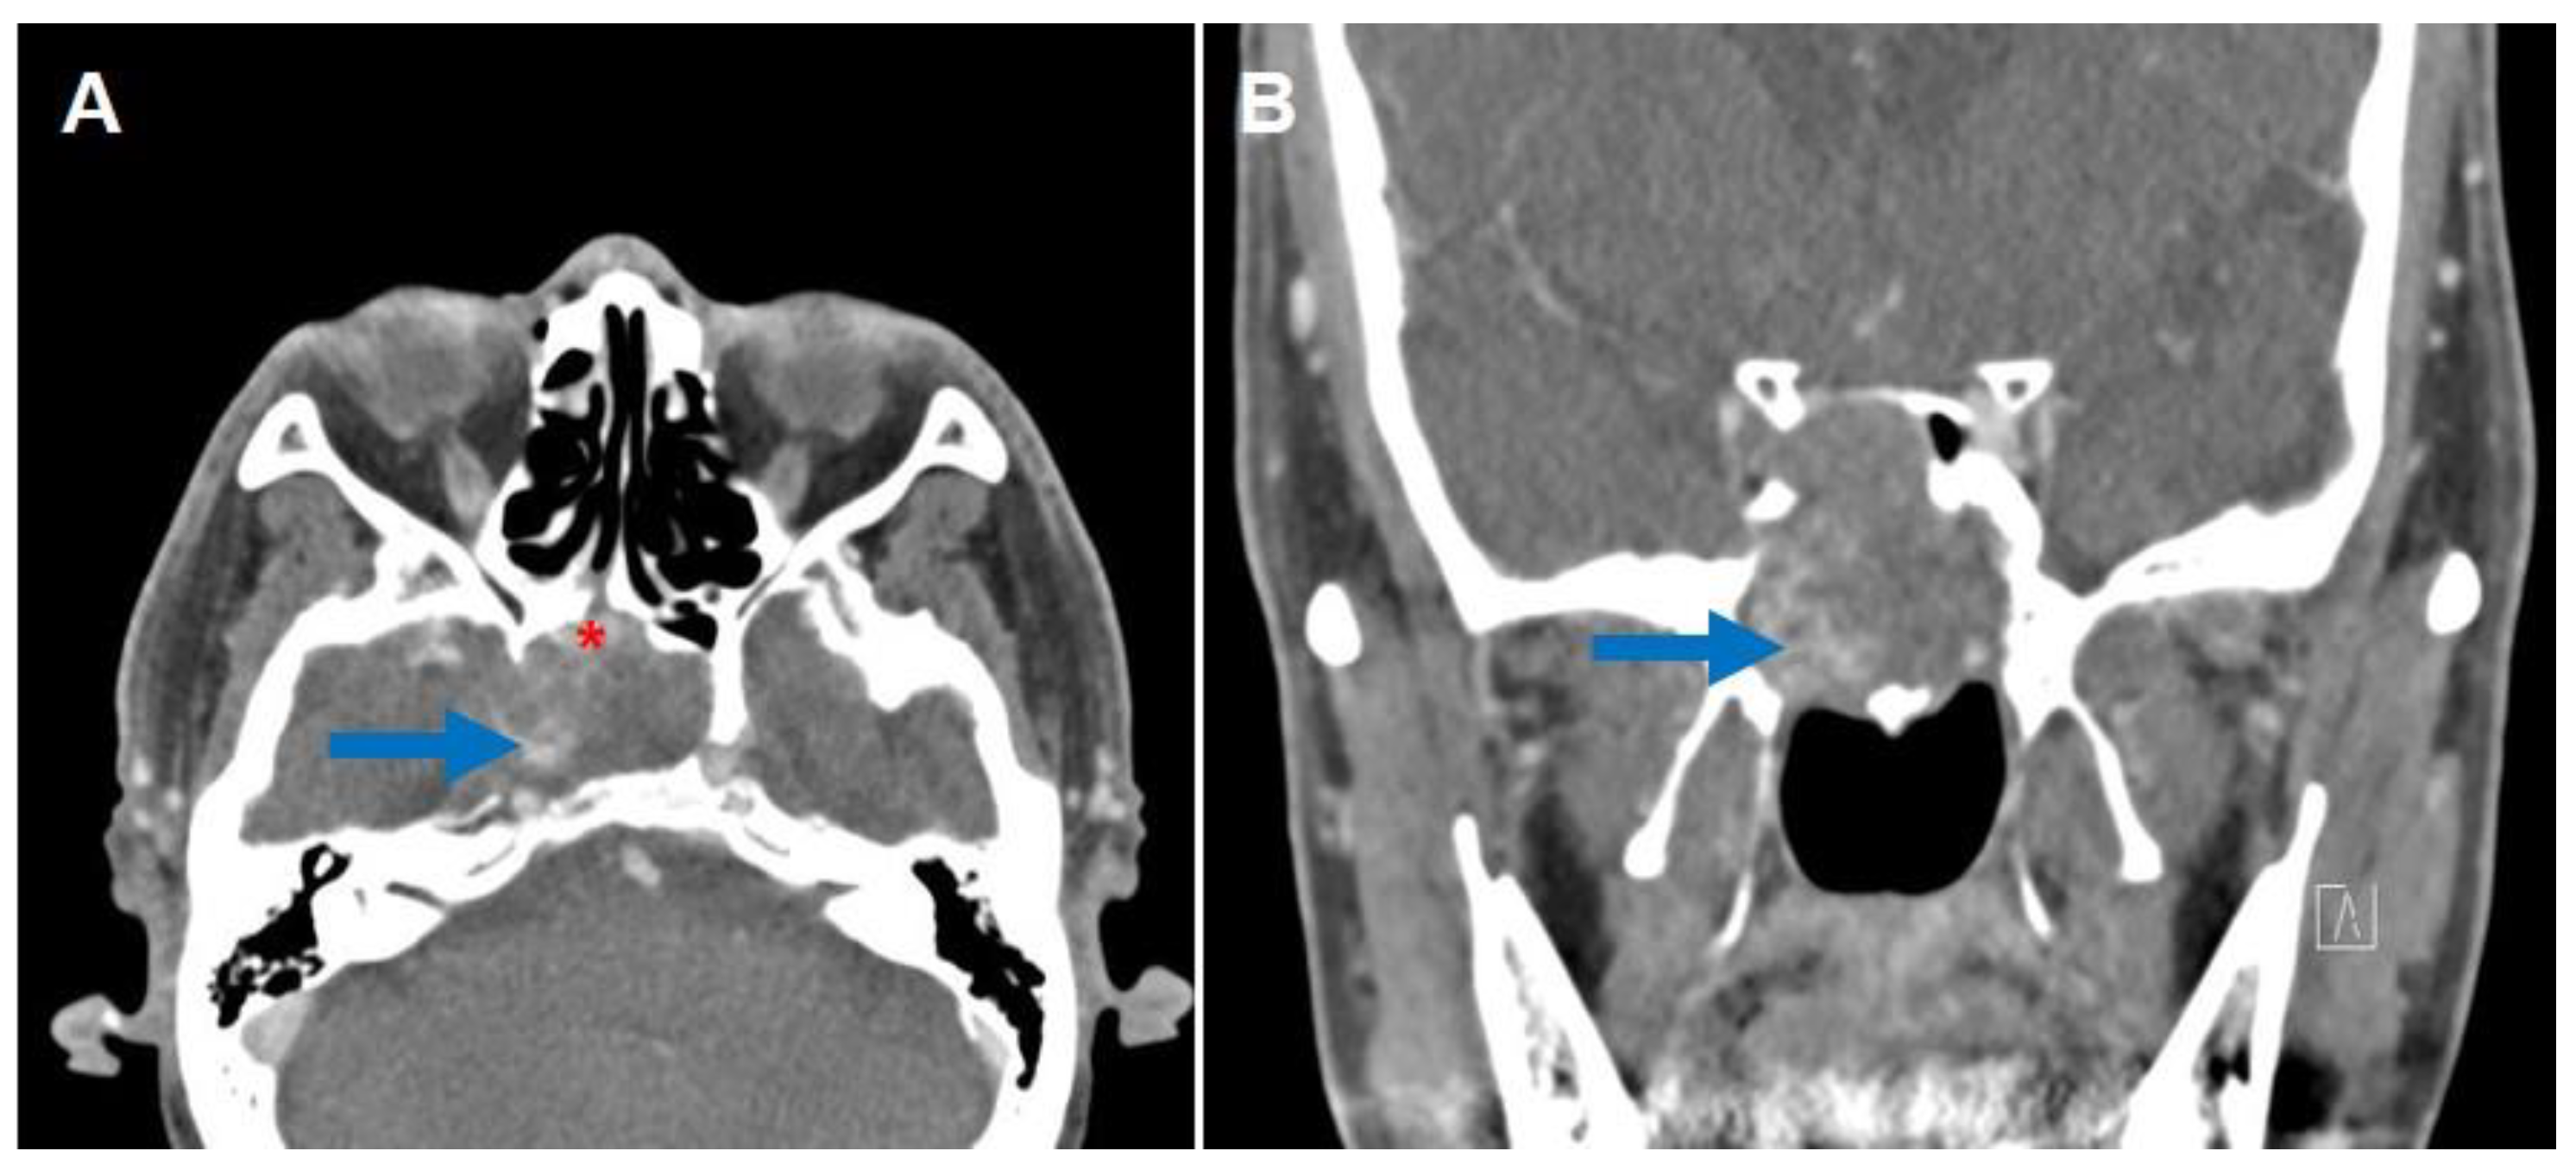

2. Case Report